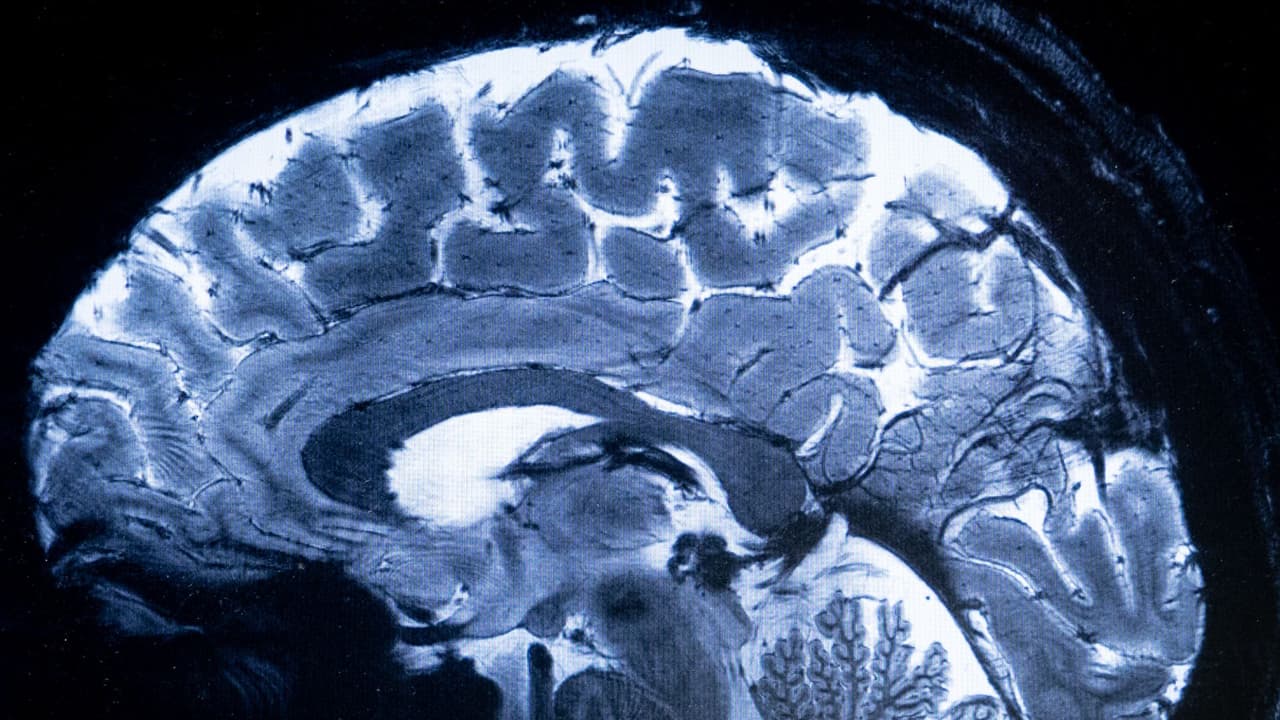

¿Sufres de fuertes dolores de cabeza? Estos son los síntomas de un aneurisma cerebral

La esposa del cantante Romeo Santos, Francelys Infante, contó que tuvo que someterse a una cirugía de emergencia tras sufrir un fuerte dolor de cabeza. Sus médicos descubrieron que tenía tres aneurismas cerebrales. La neurocirujana Jocabed Rosales explica que los pacientes pueden tener síntomas como cambios en la visión, pérdida del habla, hormigueo en el rostro y convulsiones, entre otros. Mira también: Laura Flores sufre microinfarto cerebral tras tratamiento para várices: experto explica qué pudo pasar.